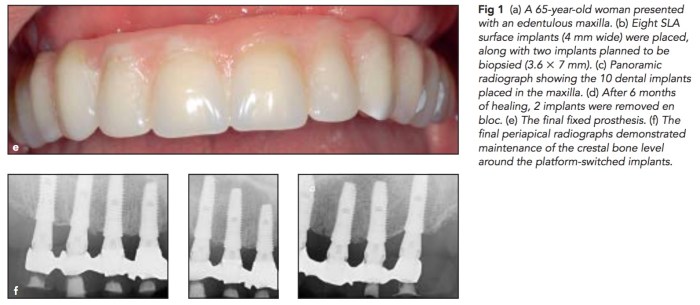

這篇研究是使用Dentium implant,它是使用SLA(sandblast with large grit and acid etched),在八個患者上做植牙全口重建的時候,額外再多種小隻的植體,然後再將這些小隻的植體拿除後去做切片看BIC(bone implant contact)。當然這樣做就是用高額的重建費用去換取研究了。結果跟之前相關的SLA implant相差不多,BIC平均有74.5%。而且在植牙之後,所有的患者都有感受到生活品質的上升。